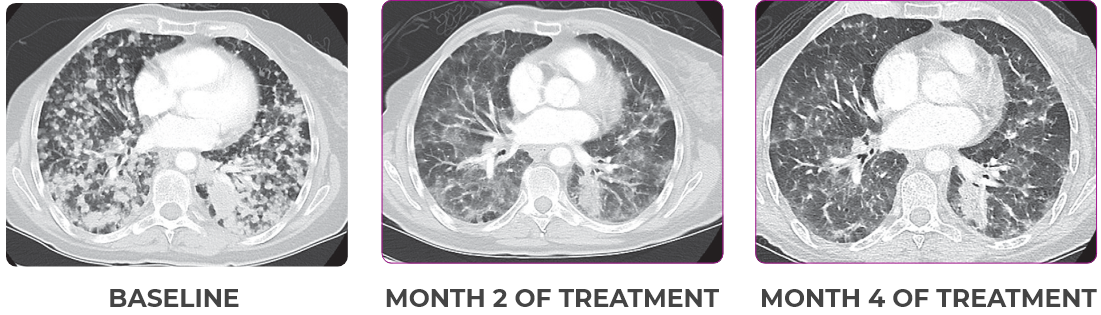

PATIENT CASE:

METASTATIC, RAIa-REFRACTORY,

PAPILLARY THYROID CANCER1,2

- 33-year-old male

- PRa after 2 cycles of VITRAKVI® (larotrectinib)

- Confirmed partial response on VITRAKVI lasting 55 cycles

Response to VITRAKVI1,2

- Confirmed partial response (92.6% reduction in target lesions)

- Treatment continued for 55 cycles

- VITRAKVI was well tolerated; patient did not have to discontinue due to AEa

- No treatment interruptions or dose reductions

Response in primary and metastatic lesions1

Images courtesy of Dr Steven Waguespack.